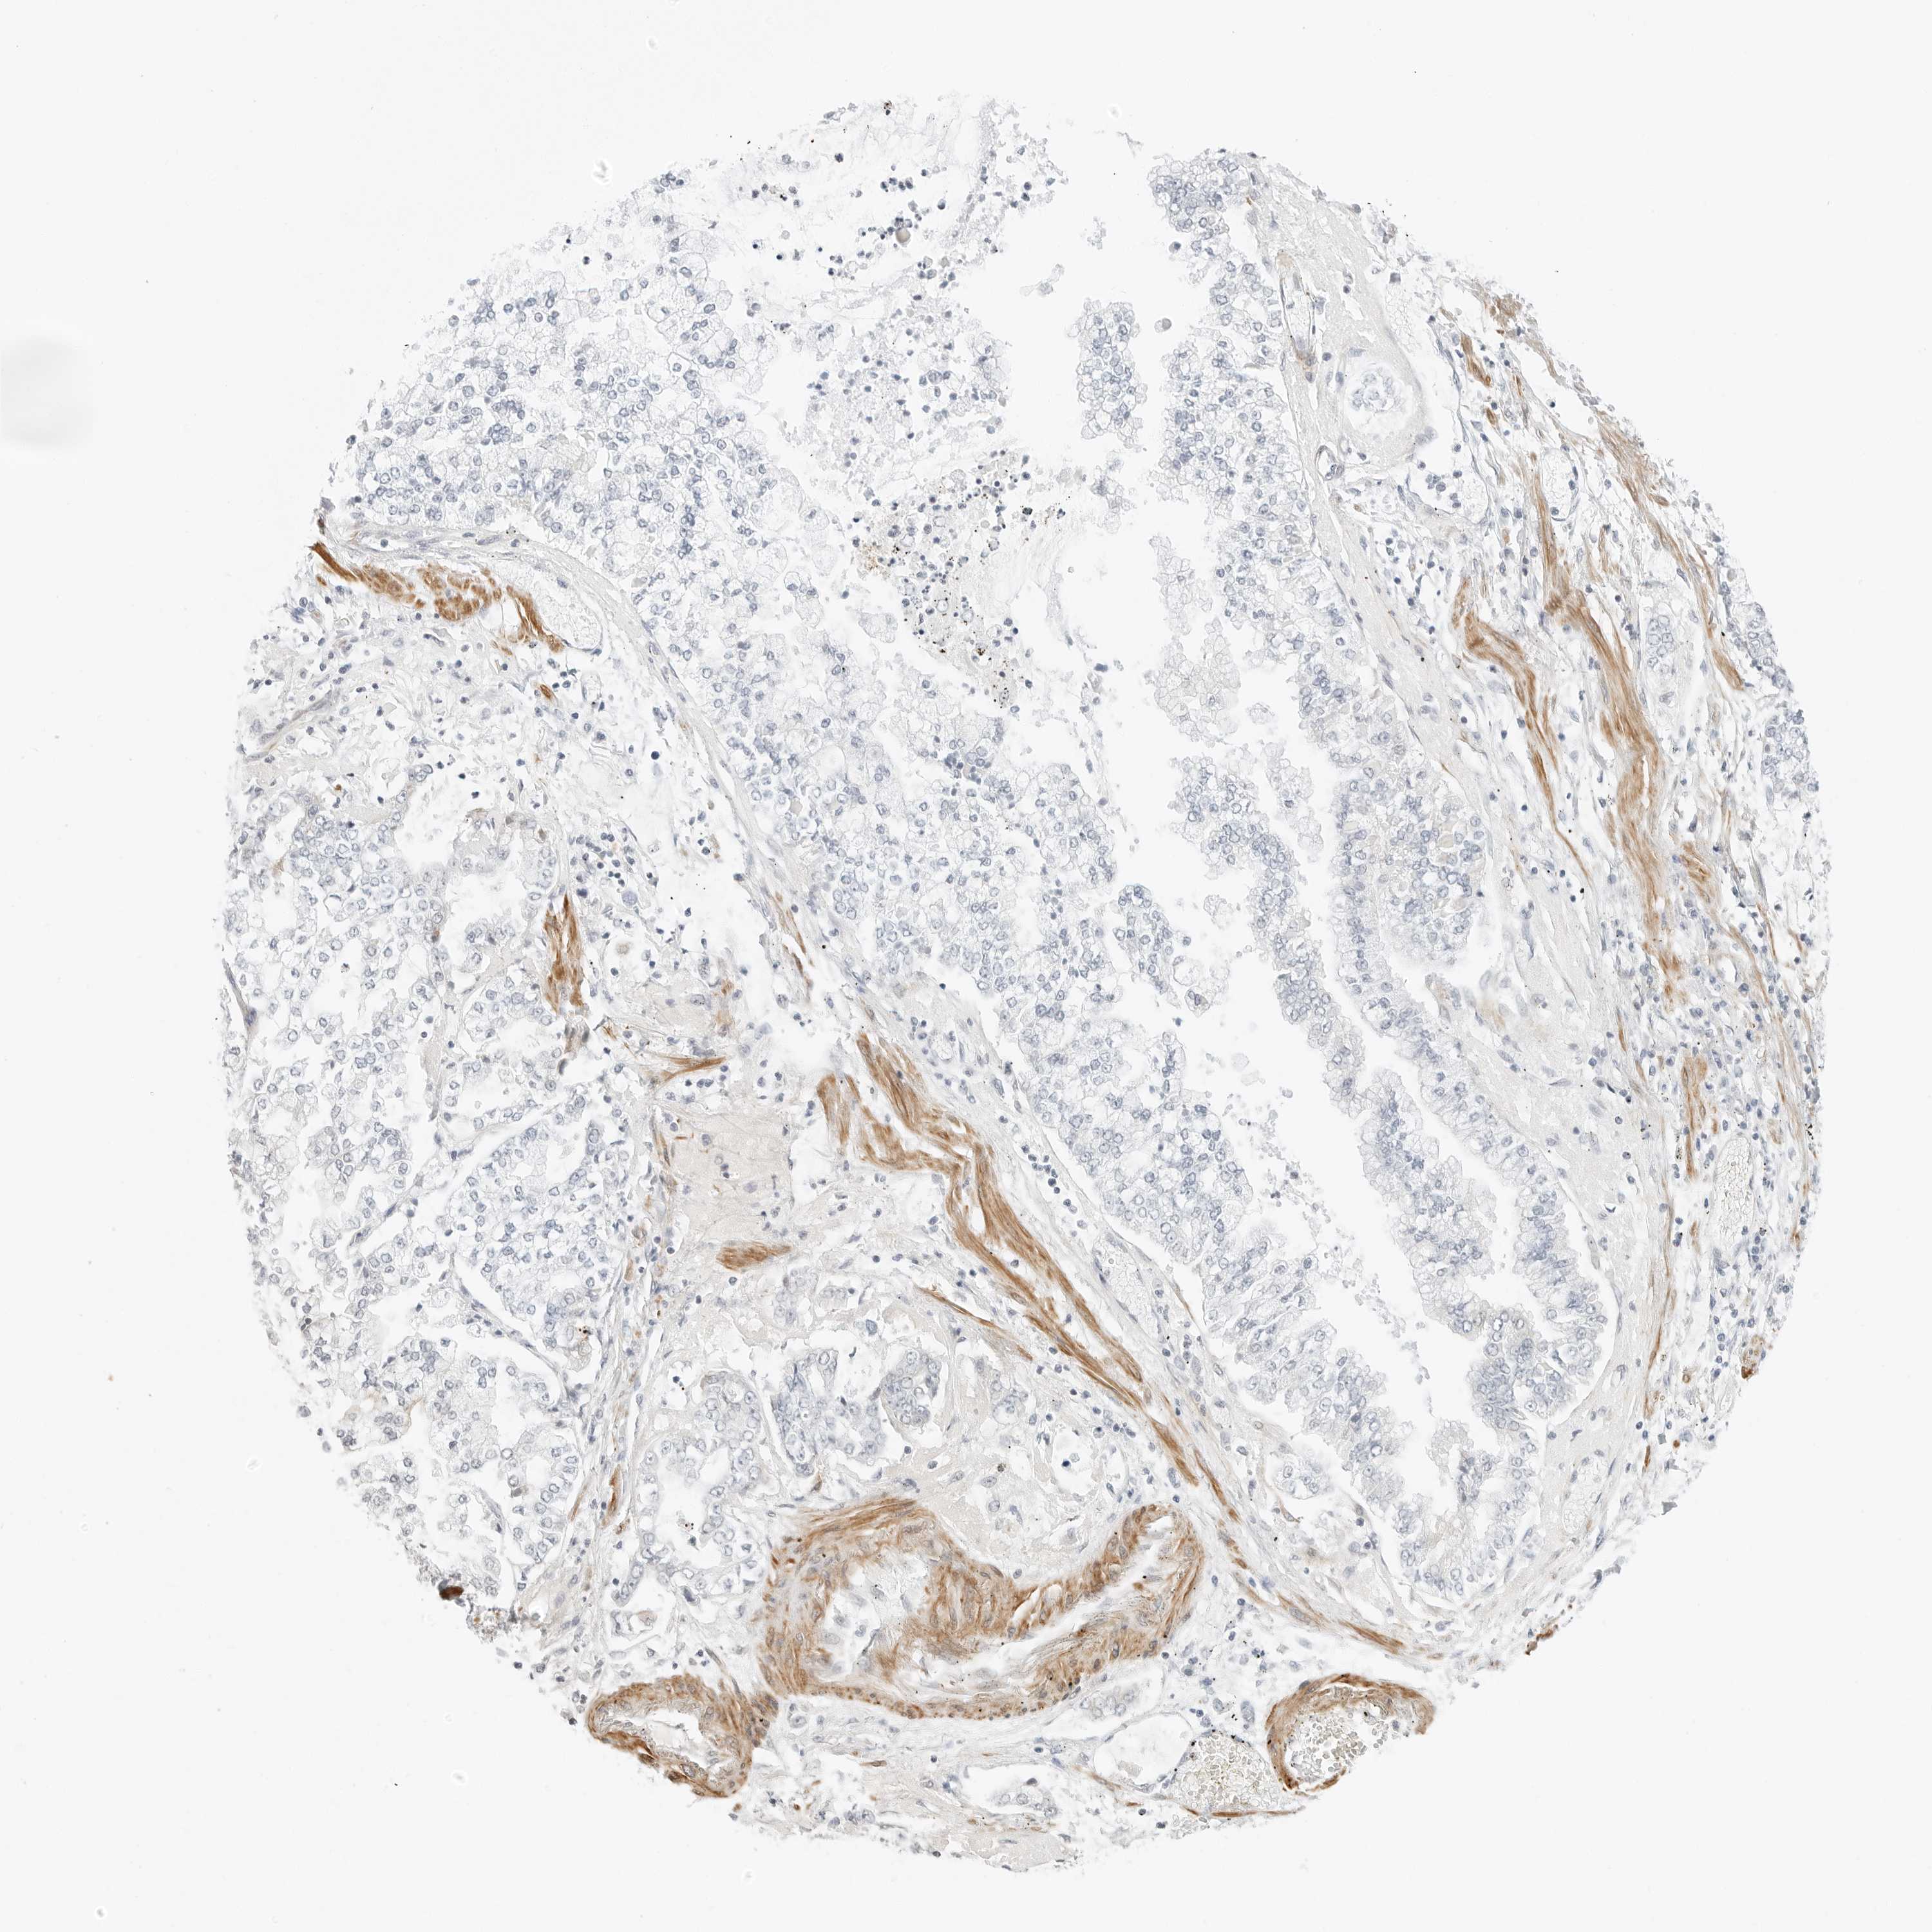

STOMACH CANCER - Protein expressioni

A mouse-over function shows sample information and annotation data. Click on an image to view it in a full screen mode. Samples can be filtered based on level of antibody staining by selecting one or several of the following categories: high, medium, low and not detected. The assay and annotation is described here.

Antibody stainingi

Antibody staining in the annotated cell types in the current human tissue is reported as not detected, low, medium, or high, based on conventional immunohistochemistry profiling in selected tissues. This score is based on the combination of the staining intensity and fraction of stained cells.

Each image is clickable and will lead to virtual microscopy that enables deeper exploration of all samples and also displays staining intensity scores, fraction scores and subcellular localization as well as patient and tissue information for each sample.

Antibody HPA028602

Antibody HPA028686

Adenocarcinoma, NOS